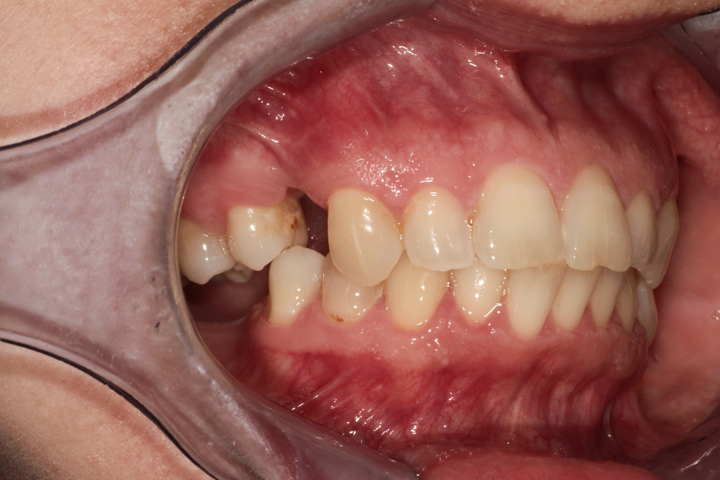

Jest to standardowa procedura wszczepiania implantu i jego odbudowy ze wszystkimi etapami pośrednimi począwszy od usunięcia zęba do cementowanej korony.